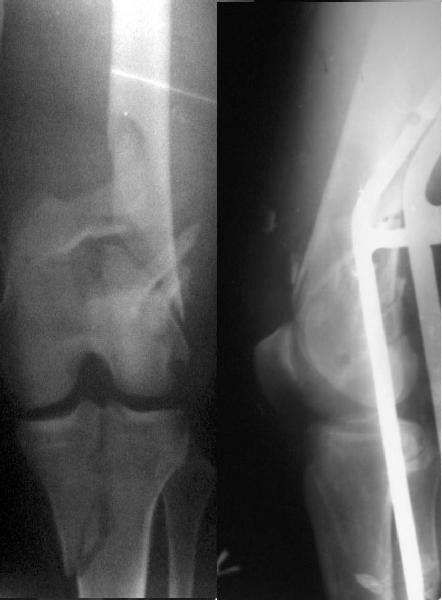

Отправитель: Zsolt Balogh 31 Октябрь 2004, 12:13

This is what we have done... As generally true for LISS look at the bone not the hardware.

There are two more srews above. The one not completely in got damaged head.